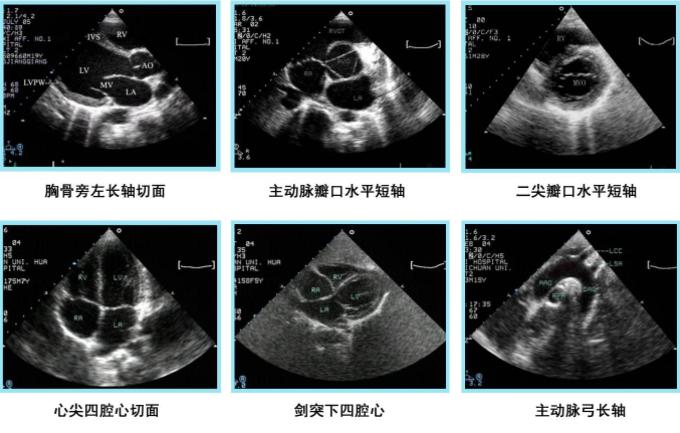

B型超声成像系统:又称超声断层法,或灰阶超声成像,目前应用Z广。光点显示,亮度随回声信号变化,深度扫描为垂直方向,位移扫描为水平方向,构成切面显示图。

M型超声成像系统:灰度调制显示,亮度显示,回波信号光点的亮度代表强弱。Z主要的特点是慢扫描电路,光点在垂直方向代表探测深度,而水平光点代表时间,由此得出一条位移-时间曲线,又称超声心动描记术。